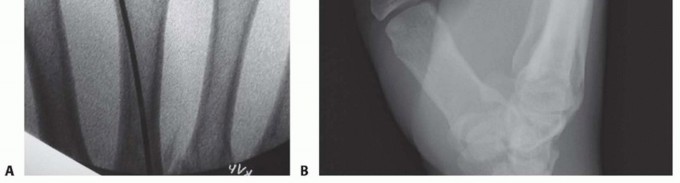

This technique requires a rotationally stable fracture that can be reduced through closed means (TECH FIG 2A).An incision is made at the base of the metacarpal. Careful dissection is carried through the soft tissues protecting the cutaneous nerve branches. The extensor tendons are retracted and the metaphysis of the base of the metacarpal is exposed.In the case of a fifth metacarpal, it is easier to make this approach straight ulnar as opposed to dorsal (TECH FIG 2B).A unicortical 2.7- or 3.5-mm tunnel is made with a drill. This tunnel is created angled in a proximal to distal direction (TECH FIG 2C).Commercially available sets include an awl that helps in establishing the tunnel through which the definitive fixation is placed.Two or three prebent wires (TECH FIG 2D) are then advanced through the tunnel, across the fracture, and lodged into the metacarpal head subchondral bone (TECH FIG 2E).Great care must be exercised advancing the wires to prevent them from penetrating through the opposite cortex.The wires can be advanced with a needle holder or a pin holder using some gentle oscillation.The hand is initially immobilized in a forearm-based splint with the MP joint in 70 to 90 degrees of flexion while allowing some motion of the IP joints.If stable fixation is accomplished early, MP joint motion is initiated. The affected finger can be buddy taped to the adjacent finger to avoid rotational forces across the fracture.The wires may be removed after 4 weeks or, if cut at the level of the bone, they may be left in place indefinitely.

TECH FIG 2 • A. Angled metacarpal neck fracture. B. Incision at the ulnar base of the fifth metacarpal, exposing the insertion of the extensor carpi ulnaris (ECU) on the base of the metacarpal. Incision located on ulnar aspect of metacarpal to minimize irritation of the extensor tendons. C. Unicortical tunnel at the base of the metacarpal. D. Sample of prebent pin. Tip is angled to facilitate passage through the shaft. E. In metacarpal neck fractures or those at risk of shortening, it is important to bring the pins to the subchondral bone of the metacarpal head but not violate the head.